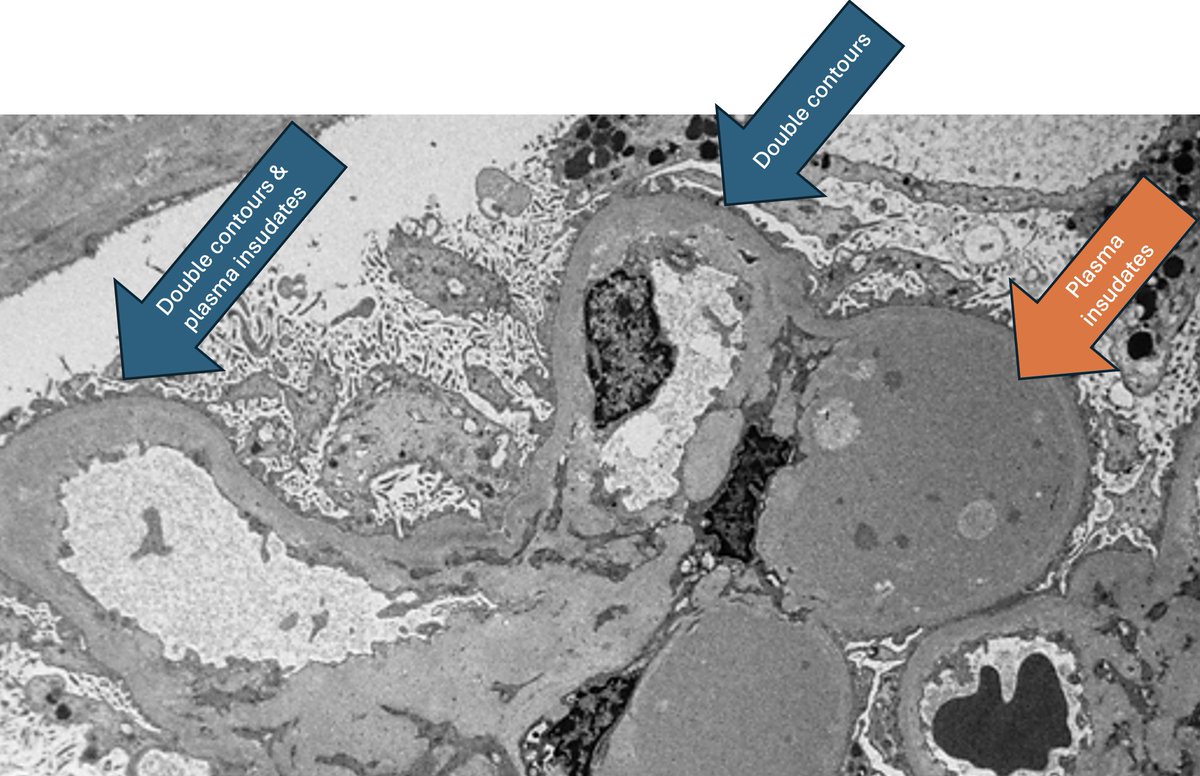

Mini case-series of crystal-storing histiocytosis (CSH) affecting predominantly glomerular loops with detailed literature review of renal CSH, images of one of the cases are depicted below, authors.elsevier.com/c/1Zh4S3uV~y8B…